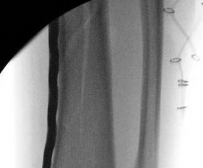

Nail Insertion and Distal Interlocking

Following meticulous preparation, the canal is reamed sequentially. Care must be taken not to over-ream the distal segment, which could compromise the already tenuous metaphyseal bone stock. The nail is inserted gently; forceful impaction is strictly avoided to prevent displacing the previously secured articular block.

Image

Distal interlocking must be maximized. The surgeon should utilize a minimum of three, and ideally four, distal locking screws, engaging the bone in multiple planes (e.g., two medial-to-lateral, one anterior-to-posterior). This multi-planar fixation is essential to control rotation and angular displacement in the wide metaphyseal bone.